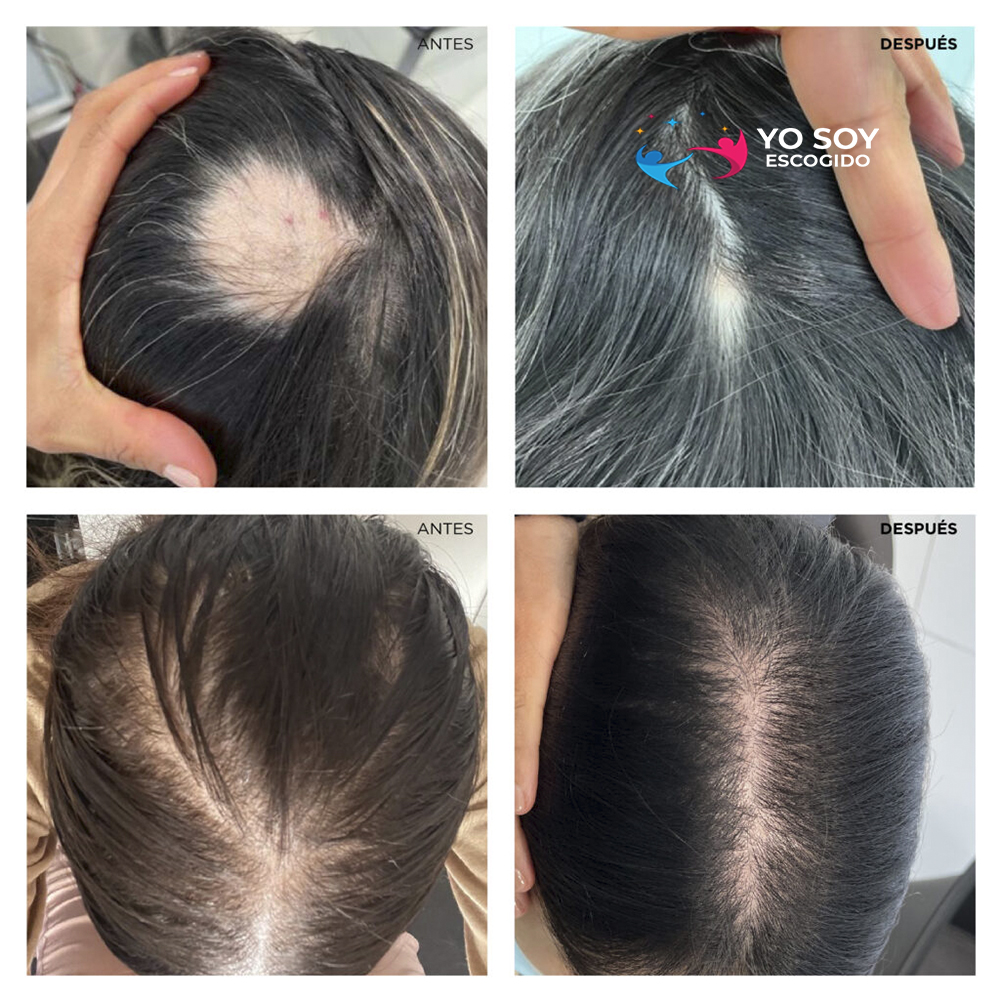

Calvicie – Tratamiento para Mujeres

Tratamiento para el crecimiento capilar en mujeres.

Reactivación Capilar